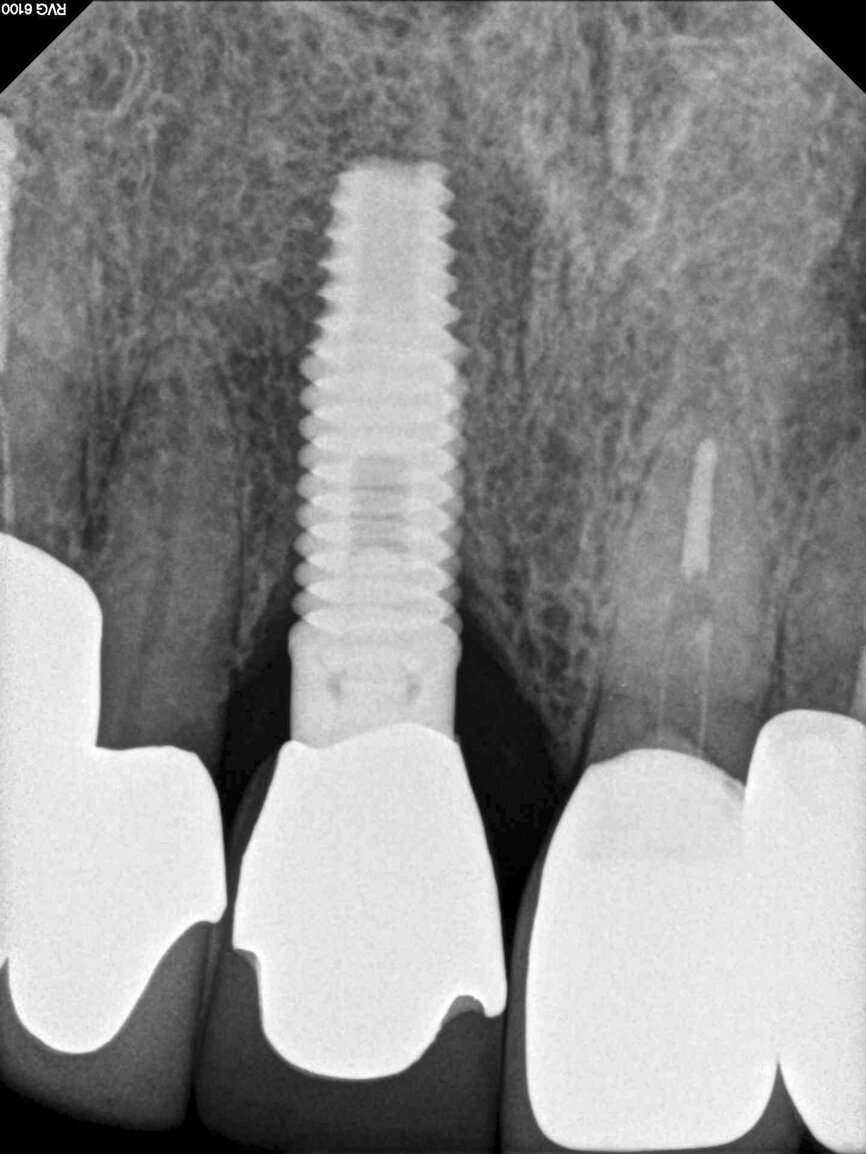

Fig. 13: The pre-op periapical radiograph revealed an existing implant-supported metal–ceramic restoration for the adjacent region #11.

A 62-year-old male patient presented with a hopeless prognosis for a post fracture in the left central incisor requiring extraction (Figs. 12a & b). The preoperative periapical radiograph revealed an existing implant supporting a metal–ceramic restoration for the adjacent region #11 (Fig. 13). The CBCT (CS 9600, Carestream Dental) cross-sectional image revealed a favourable preoperative condition relating to the trajectory of the endodontically treated root to the alveolus for a PET procedure (Fig. 14a). Using the native Carestream 3D Imaging software, a simulated implant and abutment projection was positioned within the available bone to avoid the root fragment (Fig. 14b).